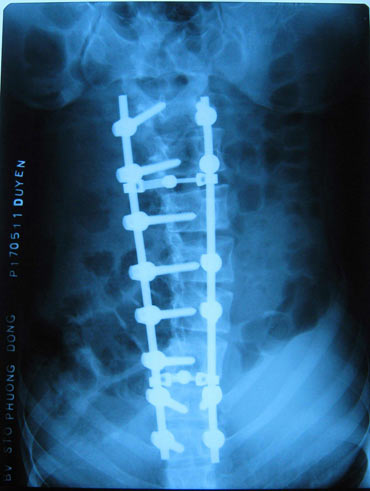

Nẹp vis và trục giữ điều trị vẹo cột sống. Ảnh: Tư liệu

Phẫu thuật điều trị vẹo cột sống là một phẫu thuật lớn, cần được chuẩn bị kỹ càng. Phẫu thuật chỉnh lại cột sống được áp dụng cho mức độ 2 mà điều trị bảo tồn không có kết quả và cho độ 3, độ 4. Nếu vẹo tới độ 4 thì phẫu thuật cực kỳ khó khăn, nẹp vis và trục giữ cột sống dùng trong phẫu thuật là những thiết bị rất đặc biệt và đắt tiền.